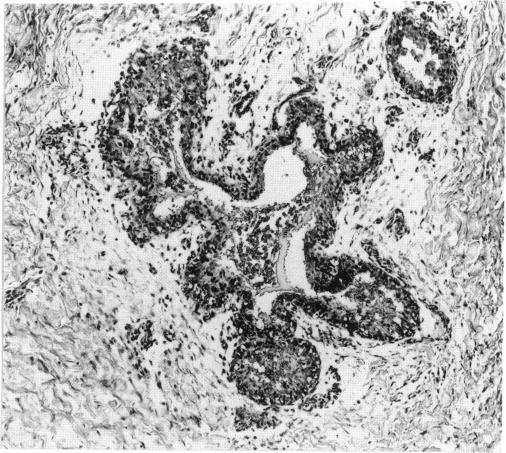

Cell proliferation has often been found to be associated with carcinogenesis in rodents and humans at different stages of the multistage carcinogenesis process. The multistage process includes initiation, promotion, and progression phases. At each phase, increasing the normal level of cell turnover of target cells may enhance carcinogenesis. However, we present evidence that normal levels of cell turnover, or increasing the rate of cell turnover at these different stages, do not necessarily lead to enhanced carcinogenesis. In normal tissues, the length of the cell cycle depends on the age of the host and varies from tissue to tissue. Tissues with normal short cell cycles, such as intestine and bone marrow, do not show a high rate of spontaneous tumors in most species. Cells with higher turnover should be more susceptible to carcinogens at the initiation stage of carcinogenesis if cell proliferation per se causes cancer and if these cells or their progeny survive. Cancer in humans is more often associated with specific etiological factors rather than with the natural proliferative rate of specific tissues. For many tissues of humans and rodents, age-related diseases develop in a progressive, irreversible manner. Often, naturally occurring chronic degenerative and inflammatory changes in a tissue (e.g., kidney, liver, heart, reproductive tract) lead to chronic regeneration of the damaged tissue. Yet, cancer is rarely found in these tissues. In rodent carcinogenesis experiments, chronic toxic lesions, accompanied by increases in normal levels of cell turnover, have sometimes been observed in target organs of nongenotoxic carcinogens. More often, however, organ-specific nongenotoxic toxins are not carcinogens. These toxins include compounds toxic for the liver, kidney, and nasal cavity. In 19 inhalation bioassays conducted by the National Toxicology Program, 5/5 nasal carcinogens and 12/14 nasal noncarcinogens caused nasal lesions usually associated with chronic cell proliferation. Although cell proliferation may contribute to multistage carcinogenesis, cell proliferation is not necessarily a tumor promoter or cocarcinogen.